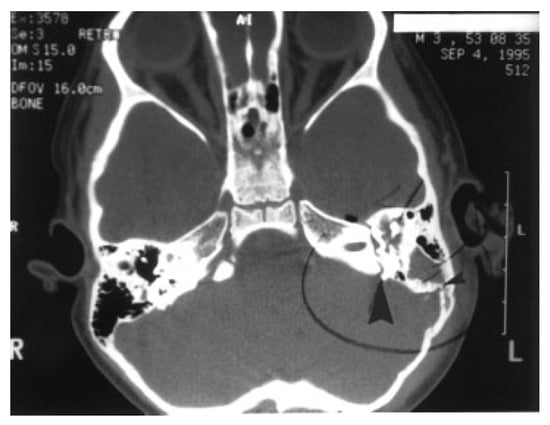

High-resolution CT scans with bone algorithms are the standard in diagnosis of temporal bone trauma. Axial and coronal thin-section CT scans can establish fracture sites in most cases, and more than one-third of fractures detected by CT are missed by clinical diagnosis alone [12]. In general, the fracture lines run parallel to the line of the blow delivered and extend through foramina, which weaken the bone. Fractures may be single or multiple and are classically referred to as longitudinal or transverse (Figure 6 and Figure 7), although careful observation demonstrates that most are actually oblique. The original terminology persists as it predicts well-known sequelae.

Figure 7. Axial computed tomography (CT) scan of the showing both a longitudinal fracture (small arrowhead) and a transverse fracture (large arrowhead) of the left temporal bone.